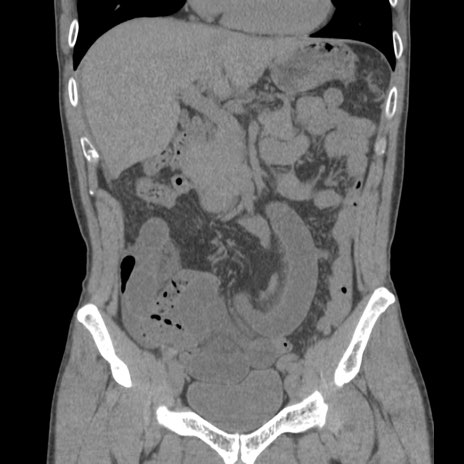

症例56 CT(冠状断像)

症例